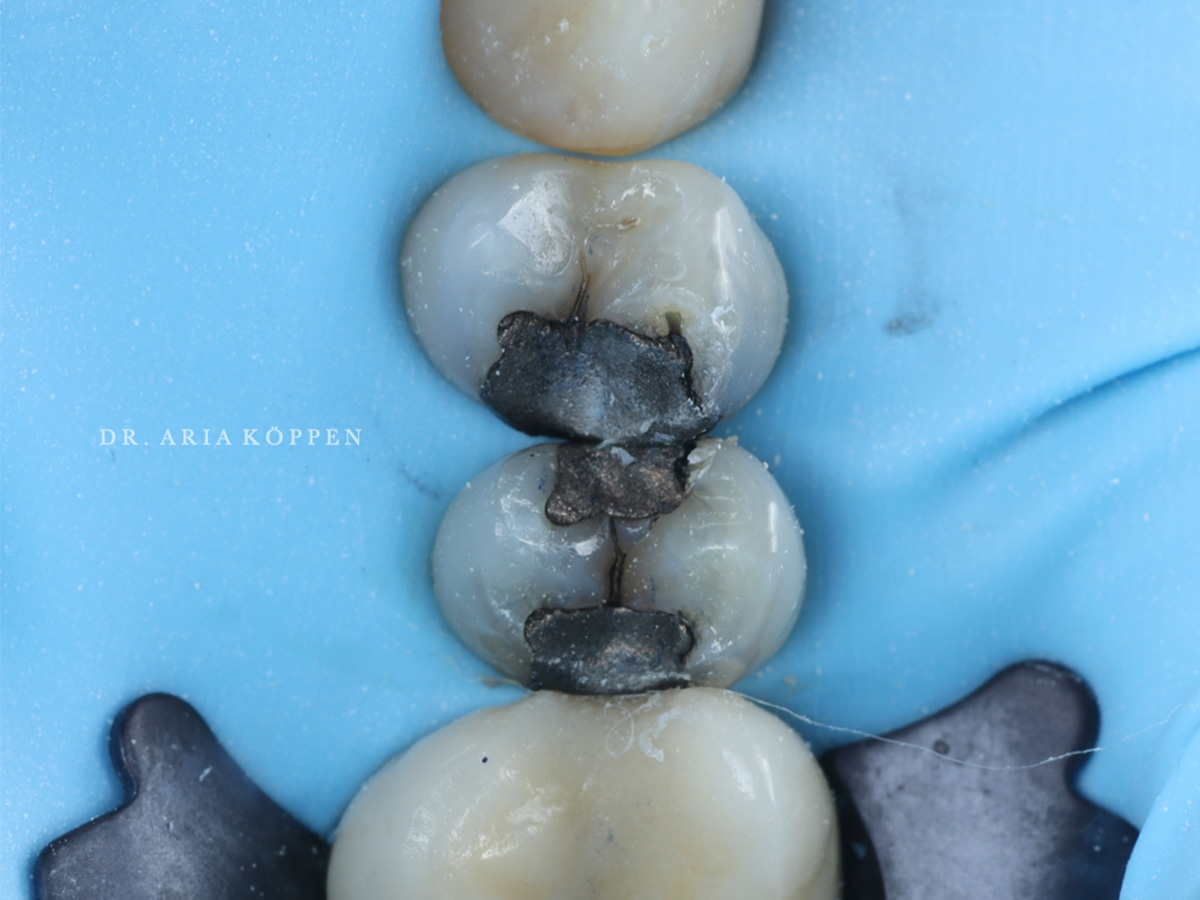

Abbildung 3

Es erfolgte die vollständige Entfernung der Amalgamfüllung sowie der darunter liegenden kariösen Läsionen. Eine saubere Peripheal Seal Zone wurde präzise präpariert. Die Schmelzränder wurden angeschrägt und die Kavitätenoberflächen mit dem AquaCare-System unter der Verwendung von Aluminiumoxid (29mikrom) abgestrahlt um einen optimalen Haftverbund der nachfolgenden adhäsiven Restauration zu ermöglichen.